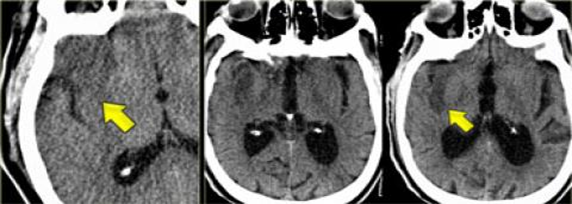

Xuất huyết não nhân bèo, thường gặp ở các bệnh nhân cao huyết áp.

Hình ảnh tăng tỷ trọng động mạch não giữa MCA bên trái, do huyết khối hoặc tắc mạch. Tương ứng với tắc MCA trên CTA.

Hình ảnh giảm tỷ trọng nhân bèo, thường liên quan đến nhồi máu động mạch não giữa MCA

Dấu“dải băng thùy đảo”. Hình ảnh này cần được phân biệt với viêm não do Herpes.